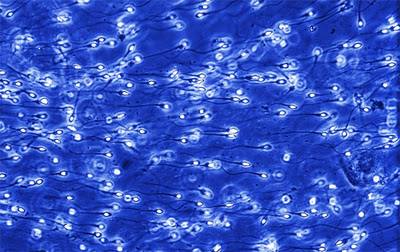

Սպերմատոզոիդ

Միլիոնավոր սպերմատոզոիդներ շարժվում են դեպի արգանդի վզիկը: